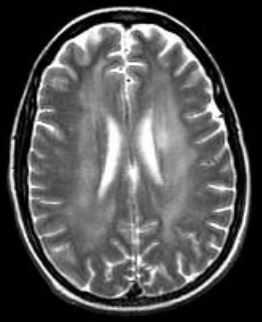

МРТ головного мозга. Аксиальная Т2-взвешенная МРТ. Расширение борозд и диффузные очаги.

Прогрессирование атрофии при прослеживании МРТ головного мозга в динамике происходит очень быстро.

МРТ головного мозга. Т2-взвешенные аксиальные МРТ типа FLAIR. Динамика очагов за полгода.